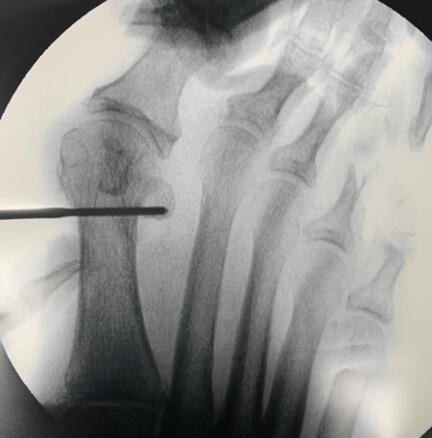

Next, the surgeon should rotate the hallux in a varus position to correct the frontal plane deformity (see fourth photo above). Once the metatarsal head is translated and the frontal plane is reduced, one can hold the reduction with the non-dominant hand. A large K-wire or Steinmann pin should capture the medial capsular tissue at the hallux and metatarsal head. This step can be performed prior to obtaining reduction of the metatarsal head to allow for easier placement into the metatarsal shaft. Following reduction, the surgeon will advance this wire intramedullary to the metatarsal base or across the first TMTJ for additional stability (see fifth photo above). Another method to maintain correction is to provisionally fixate the first metatarsal head to the second with a K-wire, with the intermetatarsal angle and tibial sesamoid position corrected. Consider lateral capsular or fibular sesamoid release if reduction is difficult. Also, consider an MIS Akin if the hallux remains in valgus or when there is an intrinsic deformity to the digit.